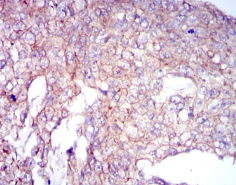

COTL1 Mouse Monoclonal antibody[5C8A5]

IHC    1/200 - 1/1000